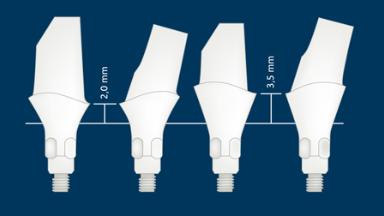

- identificar diferentes tipos de pilares de implantes

- listar diferentes materiais do pilar sobre implante e suas indicações

- selecionar pilares baseados em indicações protéticas e planejamento